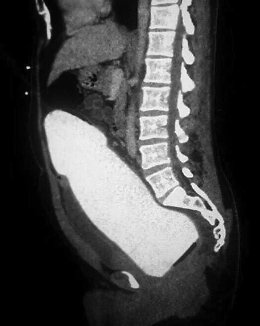

В одну из японских клиник поступил мужчина с необычной проблемой. В его прямой кишке застрял большой резиновый предмет.

Никто не предполагал, что ситуация закончится так удачно. Врачи и сам пациент б...